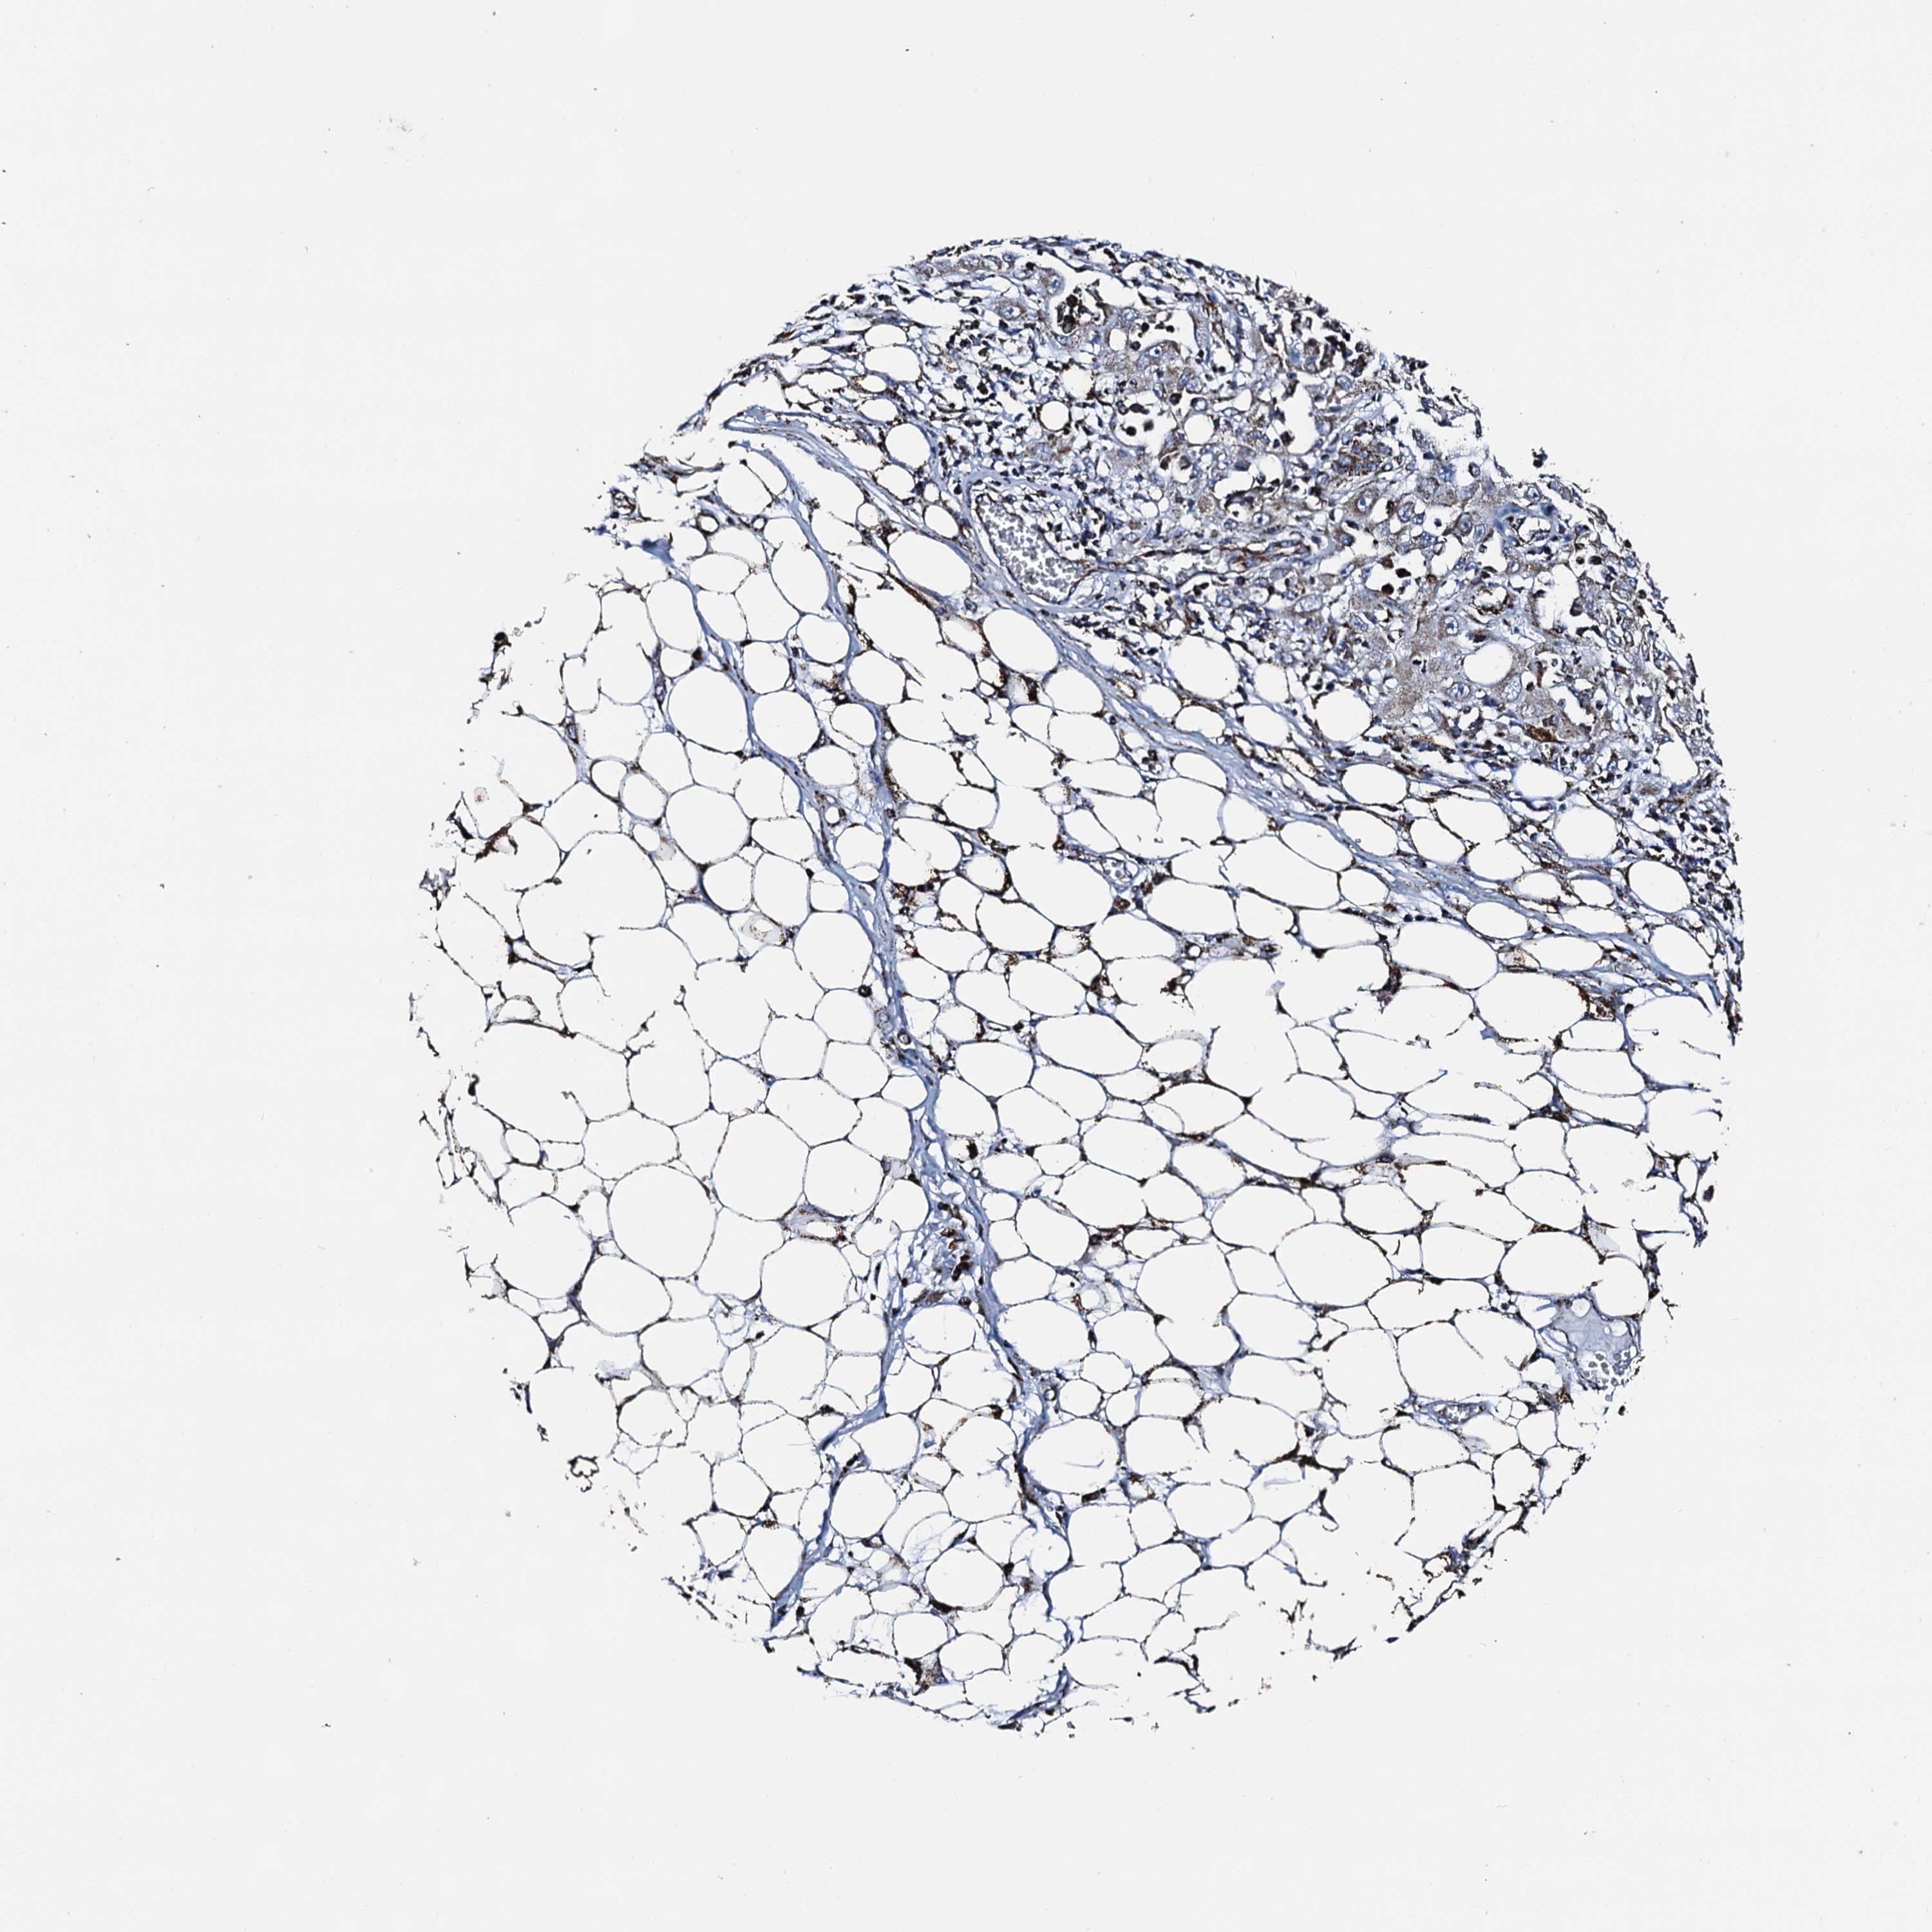

Basal cell and squamous cell cancer

SKIN CANCER - Protein expressioni

A mouse-over function shows sample information and annotation data. Click on an image to view it in a full screen mode. Samples can be filtered based on level of antibody staining by selecting one or several of the following categories: high, medium, low and not detected. The assay and annotation is described here.

Each image is clickable and will lead to virtual microscopy that enables deeper exploration of all samples and also displays staining intensity scores, fraction scores and subcellular localization as well as patient and tissue information for each sample.

Antibody HPA039588

Antibody HPA043888

Squamous cell carcinoma, metastatic, NOS

Squamous cell carcinoma, NOS